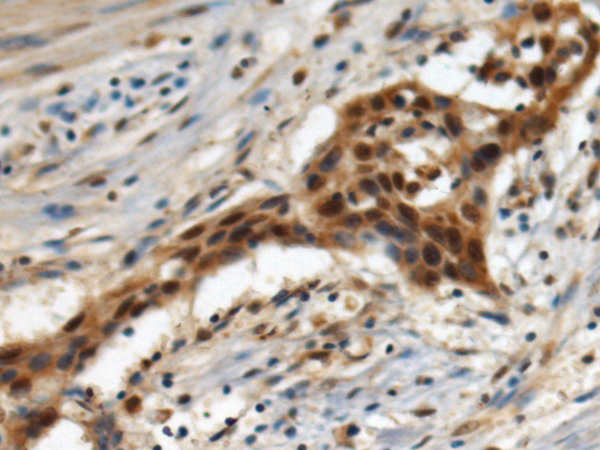

IHC positive control: |

Human esophagus cancer |